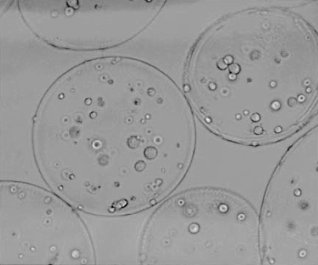

In an article that was published in Endocrinology in 2003, research leader Anthony Atala and first author Marcelle Machluf describe an experiment they did with Leydig cells from rats' testes. Leydig cells produce testosterone. The researchers gently extracted the cells from the tissue, and then attached them to globules of the polymer alginate-poly-L-lysine. The photo below shows the globules under a microscope.

The researchers performed experiments on the encapsulated cells in test tubes, and discovered that the encapsulation extended the lifespan of the Leydig cells. Ordinary cells stopped functioning after three days, but the cells in the globules – researchers call them microspheres – remained active for six days.